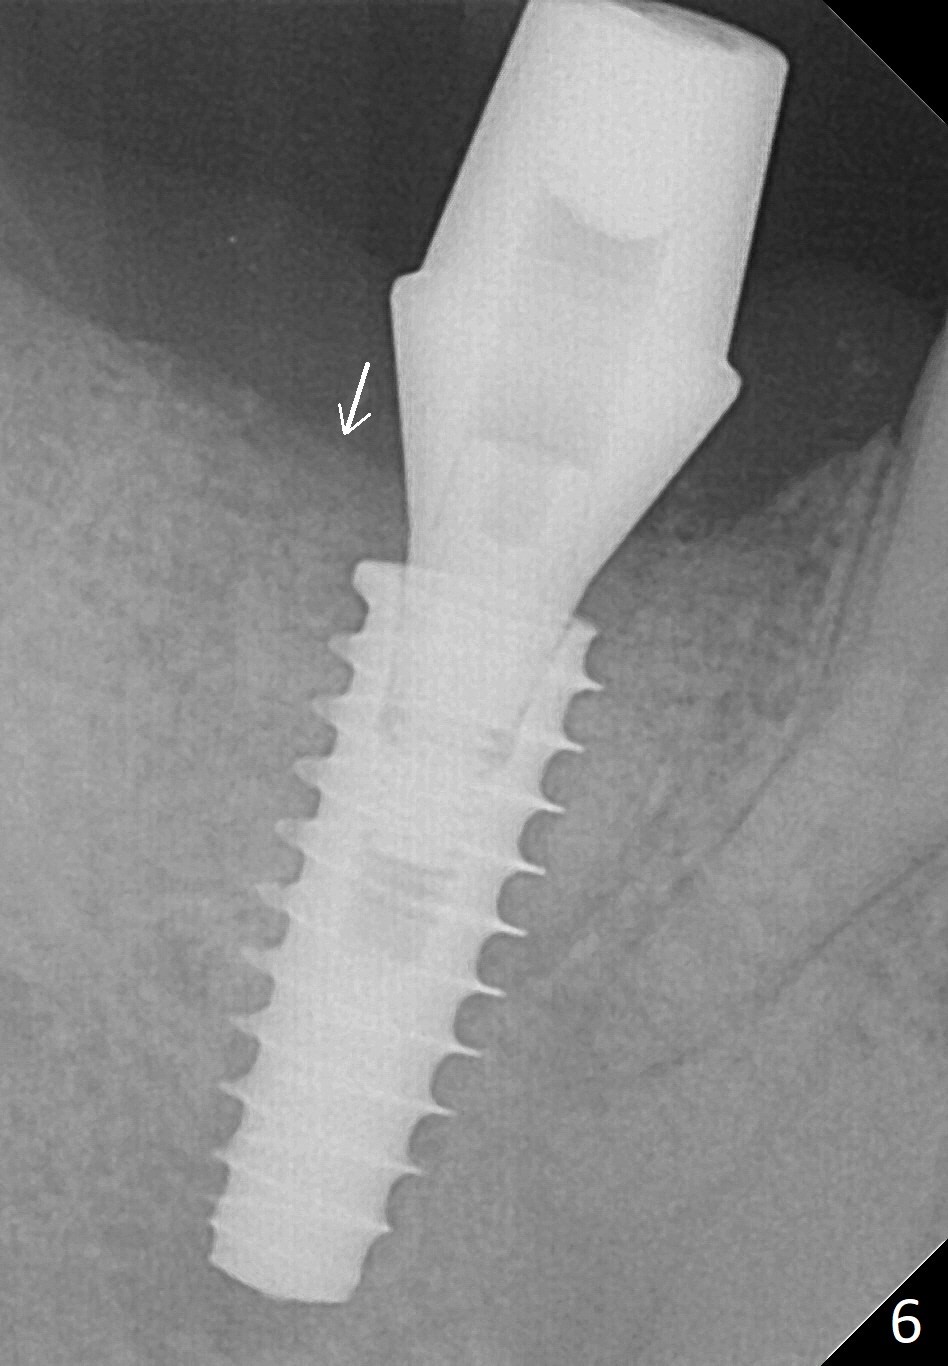

Bone graft seems to sink down and becomes denser 3 months postop (Fig.6 arrow). The bone continues being denser 5 months postop (Fig.7). There is periapical radiolucency of the tooth #29 (^). RCT is done (Fig.8). The pain persists 2 weeks postop (Fig.9,10). There is no missing canal (Fig.9). The apex is close to the implant (Fig.9 *). Apicoectomy will be performed if needed. It appears that the implant is also placed buccal (Fig.10 <) and/or the implant too large for the site. Therefore there should be a 2-3 mm buccal gap before and after implant placement. Separation and reflection of the buccal flap allows better visibility. The pain persists 1 month post RCT and 6 months post implant placement. RCT retreatment is initiated (Fig.11,12) with placement of Calcium Hydroxide paste after redebridement with 30/.04 rotary file at 23.5 mm (.5 mm longer than the earlier RCT, Fig.13). RCT retreatment finishes with apparent transportation and extrusion in 4 weeks (Fig.14,15), followed by apicoetomy (Fig.16,17) (20 days later)). Discomfort remains 2.5 months postop (Fig.18). Keep watching.